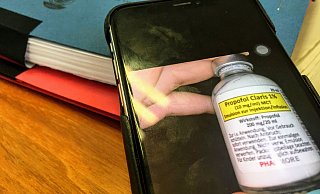

Arzt vergewaltigt Klinik-Patientinnen: Opfer entsetzt über Bethel-Ermittlungen

Ein Mediziner, der betäubte Frauen vergewaltigte, soll auch beim Personal unter Verdacht geraten sein - und vor seiner Suspendierung erhielt er ein ungewöhnliches Verbot.

Vergewaltigungen im Klinikbett: Ermittlungen gegen Bethel-Ärzte eingestellt

Nach intensiver Prüfung gibt es keinen Tatverdacht für „Beihilfe durch Unterlassen" bei den verantwortlichen Medizinern. Feministinnen kritisieren die Behörden und demonstrieren am Samstag.